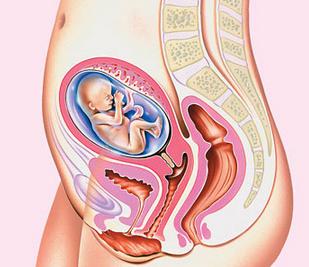

Semana 17 para la madre

En la semana 17 de tu embarazo el cuerpo empieza a sufrir cambios. Tu bebé progresa tanto, que no es de extrañar que se te claven las costuras de los tejanos. Necesitas ropa más holgada, o bien puedes optar directamente por la moda premamá. En el mercado hay una gran variedad de prendas para futuras mamás, y seguro que encuentras sin problemas las que se adaptan a tus gustos y presupuestos.

Todavía no necesitas sujetadores de lactancia, pero si que necesitarás uno de talla mayor que la normal y que además sujete bien. Un sujetador adecuado es imprescindible y, de hecho, es probable que aumentes una talla o dos varias veces durante el embarazo. Si eres de las que suelen lucir escotes generosos, prepárate para las miradas de admiración.

Síntomas de las semana 17 de embarazo

En la semana 17 de embarazo, la parte baja de la barriga ya se nota agrandada e hinchada y se ha perdido la cintura, en las piernas estas molestias son debidas a la compresión de los nervios por el crecimiento del útero, al empeoramiento en la circulación sanguínea, al incremento progresivo de la retención de líquido y a una disminución del potasio y del calcio, estos son algunos de los síntomas.

Por eso, cuando aparezca el dolor, es importante tumbarse de lado y descansar. También es habitual notar un aumento del tamaño de los pechos. Las hormonas están preparando los pechos para la producción de leche; la irrigación de sangre hacia las mamas es mayor y las glándulas que producen leche crecen y se preparan para amamantar.